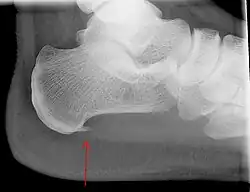

| Demonstração da fáscia plantar. Local onde ocorre a Fasceíte plantar. | |

Radiografias com visão lateral do tornozelo são a modalidade de imagem recomendada como primeira linha na investigação de outras causas de dor no calcanhar, como fratura por estresse ou desenvolvimento de esporão.[10] O espessamento da aponeurose plantar no calcanhar maior do que 5 milímetros, demonstrado por ultrassonografia, é consistente com o diagnóstico de fascite plantar.[12] Alguns autores observam que o uso de imagem não é rotineiramente necessário, já que aumenta os custos e, em geral, não altera a abordagem da fascite plantar.[15] Achados no estudo de imagens, como espessamento da fáscia plantar, podem estar ausentes em indivíduos sintomáticos ou presentes em indivíduos assintomáticos, limitando, dessa forma, a utilização de tais observações.[14] Um achado incidental associado a essa condição é o esporão de calcâneo, uma pequena calcificação óssea no osso do calcanhar, que pode ser encontrada em mais de 50% dos portadores de fascite plantar.[12] Em tais casos, é a fascite plantar subjacente que produz a dor no calcanhar e não o esporão.[14] A condição é responsável pela formação do esporão, embora o significado clínico do esporão de calcâneo na fascite plantar permaneça obscuro.[13]